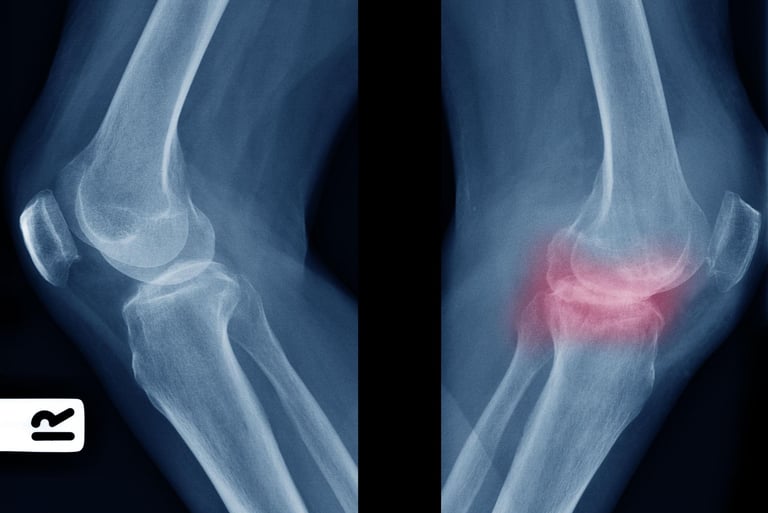

For starters, we must know what osteoarthritis is – it occurs when the protective cartilage in the joints gradually breaks down. Cartilage acts like a shock absorber, allowing bones to glide smoothly during movement. When it wears away you may feel bones starting to rub against each other, swelling of the knees and lastly joint movement becomes painful even becoming stiff. The joints that are commonly affected are the weight-bearing such as knees, hips, hands and spine. According to the World Health Organization, osteoarthritis affects over 528million individuals globally!

Many patients ignore the early symptoms. However, recognizing them early helps prevent worsening joint damage. Typical early symptoms include joint pain or after movement, morning stiffness lasting less than 30 minutes, joint tenderness when pressing the area, reduced flexibility and difficulty bending the joints, a grinding sensation when moving the joint (crepitation) and bone spurs that feel like hard lumps around the joint. In my clinic, the knee joint is the most frequently affected area.